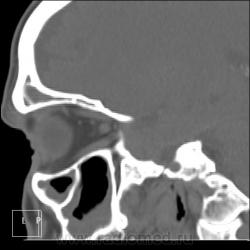

После пары менингитов на фоне синусита решили перебдеть. И вроде не зря... КТ: плотность содержимого в правой лобной пазухе 35-120 ед.Н. (мягкотканное с обызвествлением), в основной пазухе - 24 ед.Н (гнойной жидкости).

И пристеночный гайморит, и двусторонний этмоидит, и ринит, и односторонний сфеноидит, и фронтит, и очень тонкая костная пластинка между основанием передней черепной ямки и больной лобной пазухой - может быть реакция оболочек мозга...

По страшному снимку моему толком не видно, а вот на КТ множественные и разнообразные перегородки в пазухах видны хорошо. Я могу уверенно сказать только о следах жидкости в правой верхнечелюстной пазухе и субтотальном заполнении гомогенной жидкостью левой половины основной пазухи. Остальное, на мой взгляд, утолщение слизистой. Но на 100% утверждать не буду. В правой лобной я предполагаю (и только!) полипоз.

Вроде всё сказали…, но добавлю. Мне кажется, фронтит не односторонний. Эти плотные включения в правой, полипы и есть? Основных (клиновидных) пазух у каждого человека две, как и всех прочих. По обзорному снимку вижу левосторонний этмоидит. А по КТ не вижу. на каких кадрах он есть?

На 6 и 7 снимках... Справа затемнены передние ячейки решетчатых костей, слева - задние, слева процесс конечно интенсивнее.

Думаю, что полипы, "сидящие" на перегородке пазухи, сужу только по плотности - мягкотканные. А по поводу двух клиновидных пазух или разделения одной на перегородки - тут не всегда так: иногда бывает, что одна, а очень редко бывает, что и ни одной. Дайте неделю, сделаю подборку по основным пазухам на КТ.

хр.фронтит: справа с образованием обызвествленных полипообразных образований,слева- в виде утолщения слизистой оболочки. Решетчатый лабиринт клиновидной кости занят патологическим содержимым жидкостной плотности(?) с обеих сторон. Основная пазуха: справа - пристеночное утолщение слизистой, слева - тотальное заполнение. Определяется утолщение слизистой верхнечелюстных пазух, видимо воспалительного характера.